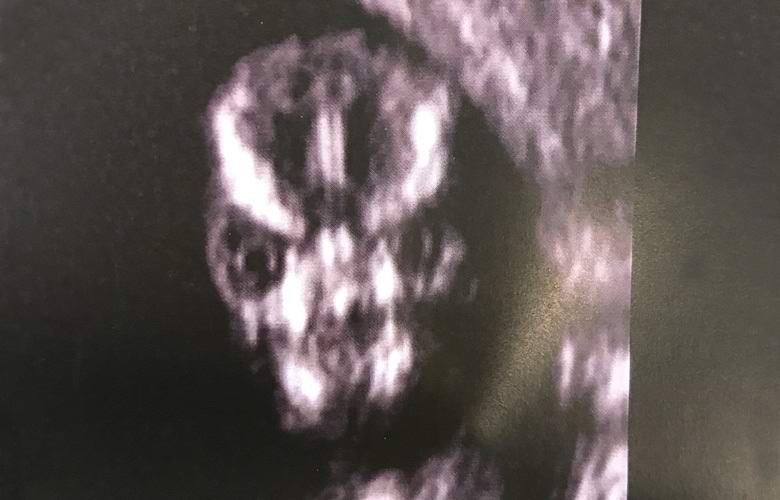

Trudna Sharney Turner posjetila je bolnicu sonografiju fetusa i primijetili žestoko lice na ekranu ultrazvučne mašine, podsjećajući je ili na jezivo čudovište, ili na vanzemaljca iz drugog planeta.

Buduća majka je odmah pitala ljekare kakav užas. Ljekari su, međutim, uvjeravali ženu, rekavši joj da je lobanja dete može imati takav izgled tokom skeniranja i nema razloga za brigu.

Specijalist za ultrazvuk odlučuje skenirati lice moj dečko i ispostavilo se da sam to bila najstrašnija stvar ikad viđeno u mom životu. Je li to zaista ljudsko izgleda li lobanja pod ultrazvukom? Zanimljivo je da je uvijek tako zastrašujuće ili je samo moja beba tako strašna?